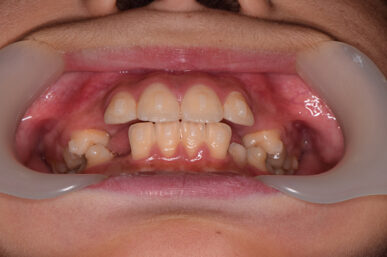

• Before

治療開始が遅くてこのままでは犬歯の生えるスペースが不足していて八重歯になるところでしたが、アライナー矯正で素早く歯を動かして犬歯が生えてくるスペースを作ることで八重歯にならずに済みました。

八重歯のケースは永久歯の抜歯が必要になることもありますが、避けることができました。

矯正後は永久歯がすべて生えるまでは予防歯科で歯の生え代わりと機能を管理します。